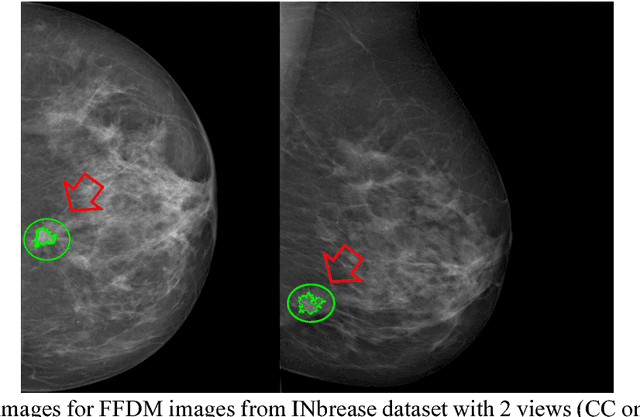

Abstract:Breast cancer is the second leading cause of cancer death among women worldwide. Nevertheless, it is also one of the most treatable malignances if detected early. Screening for breast cancer with digital mammography (DM) has been widely used. However it demonstrates limited sensitivity for women with dense breasts. An emerging technology in the field is contrast-enhanced digital mammography (CEDM), which includes a low energy (LE) image similar to DM, and a recombined image leveraging tumor neoangiogenesis similar to breast magnetic resonance imaging (MRI). CEDM has shown better diagnostic accuracy than DM. While promising, CEDM is not yet widely available across medical centers. In this research, we propose a Shallow-Deep Convolutional Neural Network (SD-CNN) where a shallow CNN is developed to derive "virtual" recombined images from LE images, and a deep CNN is employed to extract novel features from LE, recombined or "virtual" recombined images for ensemble models to classify the cases as benign vs. cancer. To evaluate the validity of our approach, we first develop a deep-CNN using 49 CEDM cases collected from Mayo Clinic to prove the contributions from recombined images for improved breast cancer diagnosis (0.86 in accuracy using LE imaging vs. 0.90 in accuracy using both LE and recombined imaging). We then develop a shallow-CNN using the same 49 CEDM cases to learn the nonlinear mapping from LE to recombined images. Next, we use 69 DM cases collected from the hospital located at Zhejiang University, China to generate "virtual" recombined images. Using DM alone provides 0.91 in accuracy, whereas SD-CNN improves the diagnostic accuracy to 0.95.